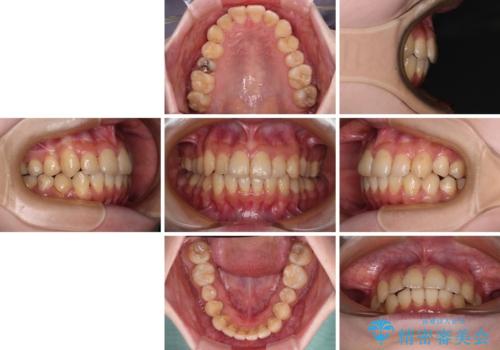

デコボコ歯列をきれいに インビザラインによる矯正治療

- 2年8ヶ月

- 上下歯列全体のデコボコを気にして来院された患者様です。

主に下顎歯列全体の後方移動とIPR(歯と歯の間を削る)によってデコボコが解消するように設計し、インビザラインにより治療を行うこととしました。

奥歯の知覚過敏が顕著となり、その影響で奥歯の咬み合わせ改善のための顎間ゴムの装着ができず、咬合を仕上げるまでに長い期間を要することとなりました。